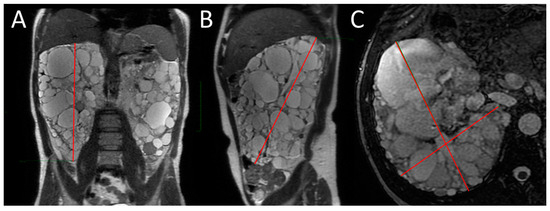

SSFP and SSFSE acquisition planes were used for the evaluation of kidney volume through the ellipsoid method (Figure 1). The diameters of kidneys were measured in millimetres, and the online calculator tool developed by the Mayo Clinic and freely available on the Mayo website [14,18] was used to calculate the SKV and the TKV. For patients with only one native kidney, TKV coincided with the volume of the single kidney. Volumetric segmentation (Figure 2 and Figure 3) was performed using a dedicated workstation (Advantage Workstation 4.6 General Electric; GE Healthcare, Milwaukee, WI, USA).

Figure 1.

MRI measurement of renal diameters on the right kidney of a patient with ADPKD for SKV computation using the ellipsoid method. Coronal length (A), sagittal length (B), width and depth (C).